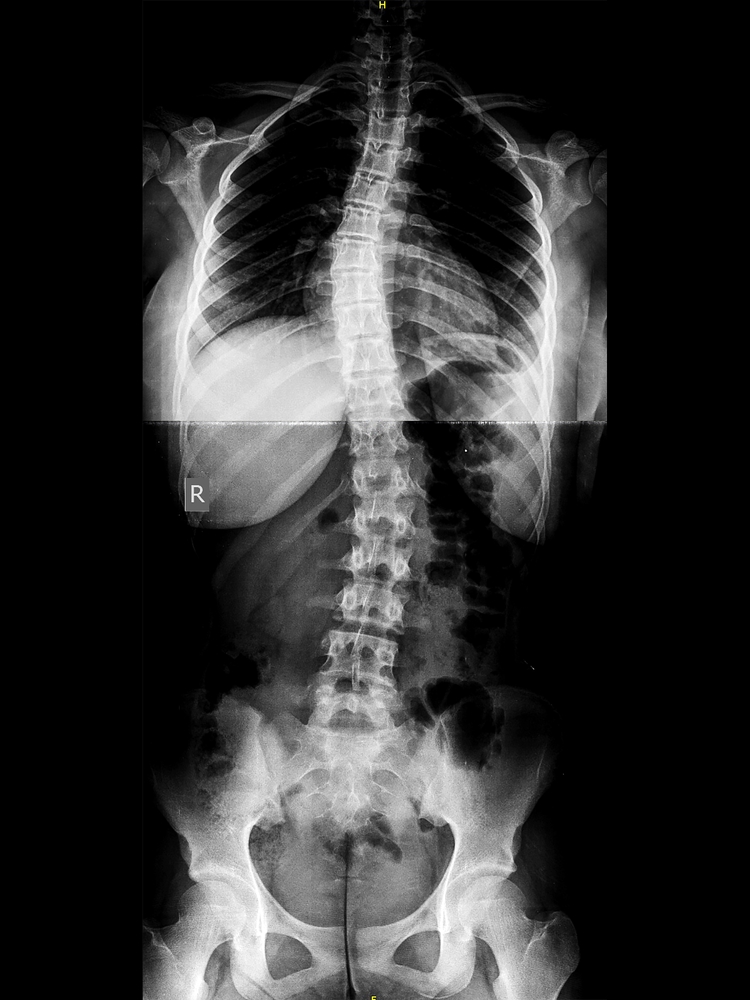

Scoliosis Rehabilitation

Non-surgical scoliosis management through scoliosis-specific exercises (e.g., Schroth method principles), spinal alignment correction, and respiratory training.